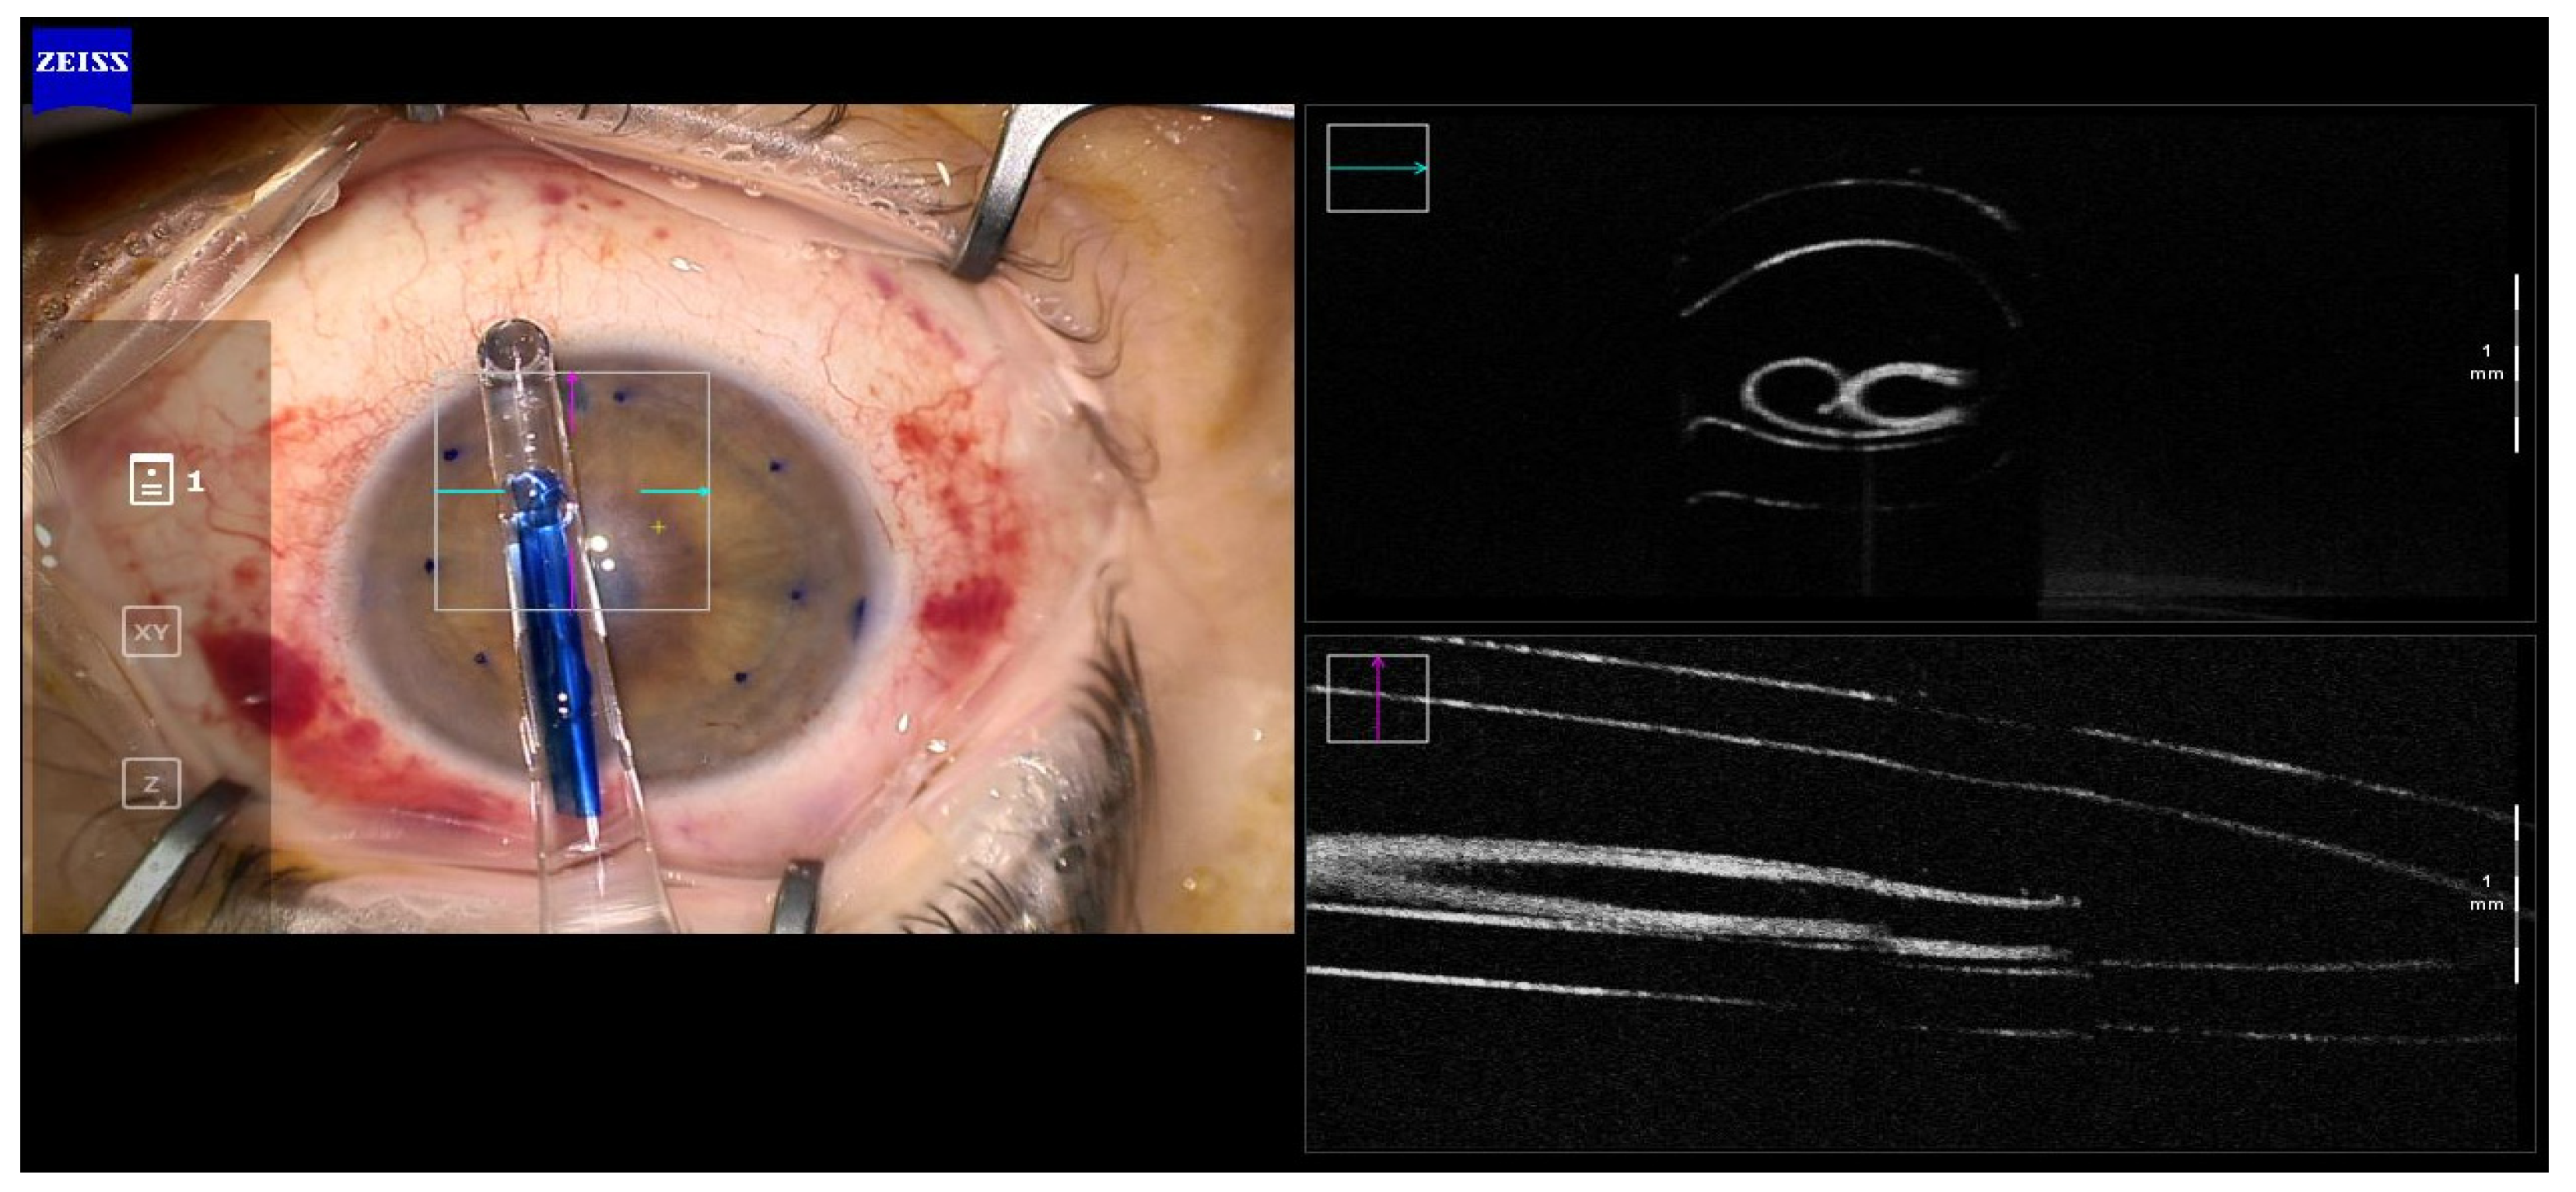

Surgical Technique